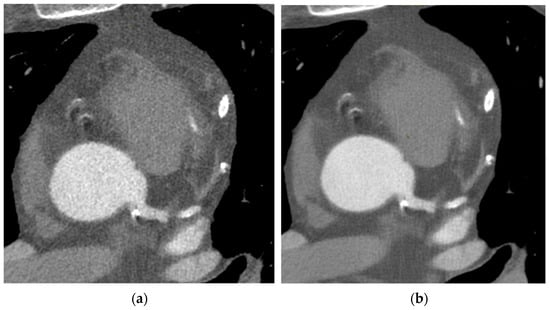

As we can see in Figure 1, the DLIR (b) shows image quality improvement with reduced image noise and better-defined anatomical details, when compared with the ASIR-V(a).

In fact, the contrast enhancement of the aorta and the left coronary artery is more homogeneous with the disappearance of multiple small areas of hypodensity and a consequent better visualization of the vessels’ boundaries and internal structure, which are the fundamental details in the study of the coronary wall.

Radiologists have found that coronary arteries have better visualization in both calcified and soft plaques, which leads to a higher level of confidence when assessing stenosis.

The images also show an improvement in the measurement of the bifurcation angle on the three-dimensional volume-rendered image of the coronary artery tree.

Figure 1. Clinical images of a patient’s CCTA sequence reconstructed with the ASIR-V algorithm at 60% (a) and DLIR algorithm at high level (b).